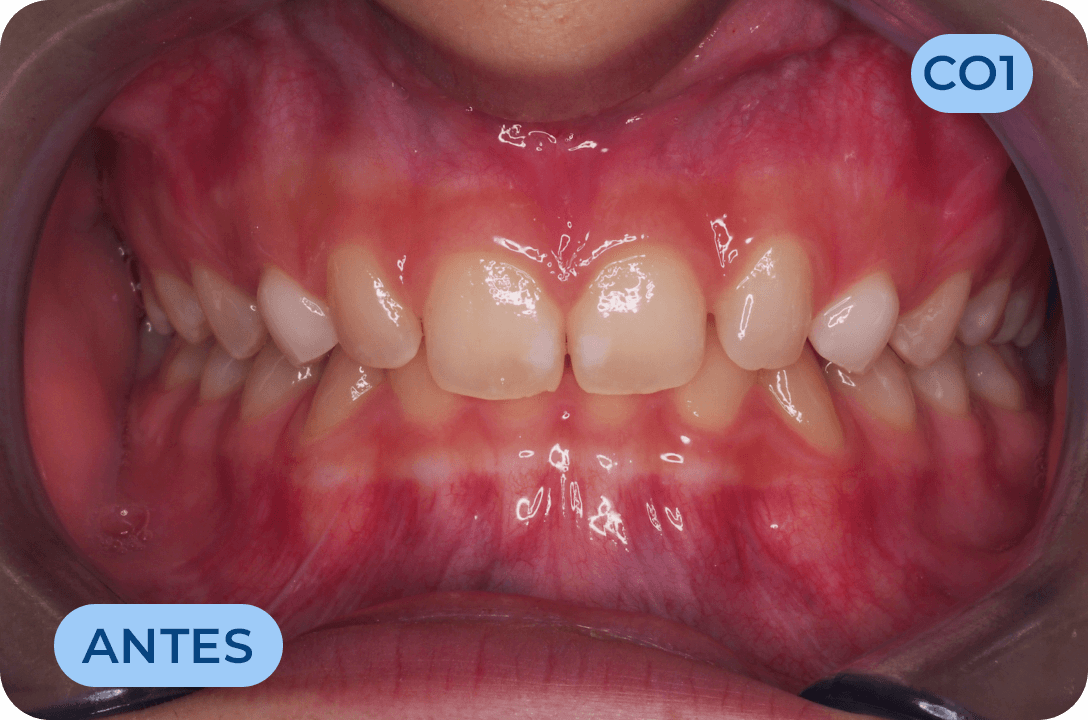

Ortodontia

É a especialidade da Medicina Dentária que se debruça sobre o estudo e correção das más posições dentárias e dos maxilares. Atualmente é possível tratar pacientes de todas as idades, no entanto a 1ª consulta deve ser realizada ainda na infância para intercetar eventuais problemas de desenvolvimento esquelético e funcional.